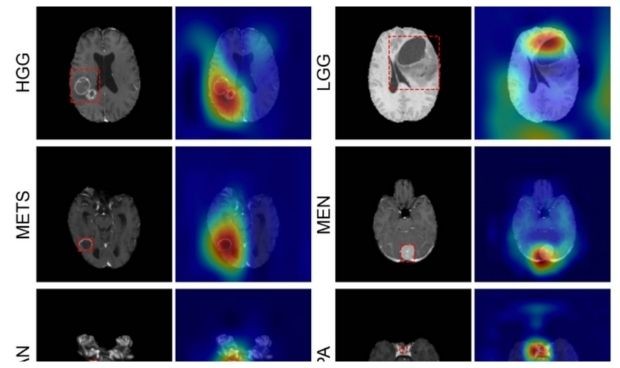

Mapas de atención aproximados generados con GradCAM para glioma de alto grado (HGG).

Con los datos de las pruebas internas, el modelo logró una precisión del 93,35 por ciento (337 de 361) en siete clases de imágenes (una clase sana y seis clases de tumores). Las sensibilidades variaron del 91 por ciento al 100 por ciento y el valor predictivo positivo (o la probabilidad de que los pacientes con una prueba de detección positiva realmente tengan la enfermedad) varió del 85 por ciento al ​​100 por ciento. Los valores predictivos negativos, o la probabilidad de que los pacientes con una prueba de detección negativa realmente no tengan la enfermedad, oscilaron entre el 98 por ciento y el 100 por ciento en todas las clases. La atención de la red se superpuso con las áreas tumorales para todos los tipos de tumores.